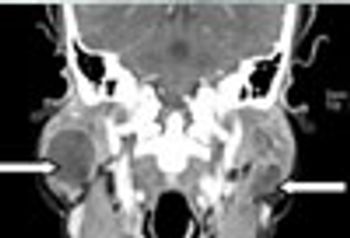

The top men's health concerns include heart disease, cancer, accidents, and chronic lower respiratory diseases. This compact slide show provides visual presentations of other clinical problems that pose a threat to men and that might be seen in primary care practice.